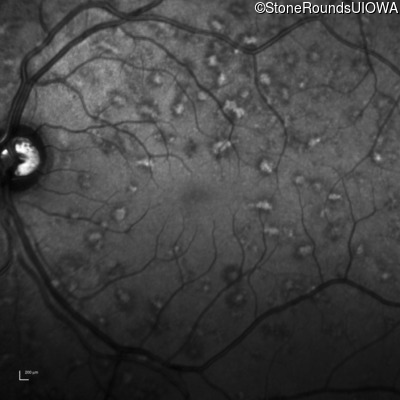

AR Stargardt Disease (IIA)

OD OS

This 30 year old asymptomatic man had fundus abnormalities identified incidentally on a routine exam.

Age at visit: 32 years

Diagnosis & molecular findings

Disease Gene Allele 1 variant(s) Allele 2 variant(s) Inheritance mode

AR Stargardt Disease ABCA4 IVS30+1321 A>G Asn965Ser AAT>AGT AR